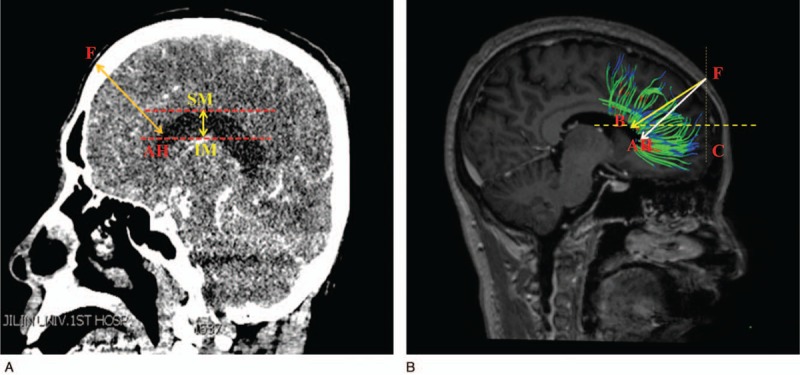

All the CT imaging data were taken by a CT machine (GE Sigma HDxt; GE, Fairfield, CT) in Department of Radiology, the First Hospital of Jilin University. Then, the imaging data were reconstructed using the volume-rendering system to conduct a measurement. The measurements were performed on the coronal, sagittal, and axial planes after three-dimension reconstruction in computer, respectively. After all the anatomical structures were identified, the sagittal plane was selected to make the measurements (as shown in Fig. 1A). The shortest distance (FAH) from the frontal puncture point (F) to anterior horn of the lateral ventricle (AH) was measured, and the vertical distance of the lateral ventricle was also measured. The vertical distance of the lateral ventricle was defined as the distance from inferior margin (IM) to superior margin (SM) of the lateral ventricle in sagittal plane. Then, the horizontal plane of the samples was selected (as shown in Fig. 2A), we also measured the shortest distance (OPH) from the occipital puncture point (O) to the posterior horn of the lateral ventricle (PH) as well as the length of the lateral ventricle, the length of the lateral ventricle was defined as the distance from anterior margin (AM) to posterior margin (PM) of the lateral ventricle in axial plane. What's more, the other sagittal plane of the samples was selected as an innovative method brought out in this study, the puncture line was chosen by parallel to the most of never fiber bundles (PM) (as shown in Fig. 3A), we measured the shortest distance PPH from the parietal puncture point (P) to the posterior horn of the lateral ventricle (PH) as well as the distance of the lateral ventricle from IM to SM of the lateral ventricle in sagittal plane.

Figure 1.

(A) The data and the puncture point from frontal lobe in computed tomography image. (B) The puncture point and angle in diffusion tensor image.

Image processing: DSI studio was used to analyze the image and to reconstruct the FA, VR, RA, ADC, and color FA map. By comparing and analyzing the section images, FA and color FA map, the location and form of the white matter fiber bundle as well as the lateral ventricle were identified and measured. After all the anatomical structures were identified, the reconstructed whole brain never fibers was displayed (as shown in Fig. 4), the axial parameters S, P, and L noted superior, posterior and left, respectively. The sagittal plane of the samples which reconstructed partial never fibers near the frontal lobe was selected (as shown in Fig. 1 B), we measured the shortest distance FAH from the frontal puncture point (F) to the anterior horn of the lateral ventricle (AH), the distance FB from the puncture point (F) to the point B which was determined by the direction parallel to the fiber bundles. In this way, FB was parallel to the shape of fiber bundles. FB is the refined puncturing angle that was firstly brought out in this study, whereas FAH was the traditional puncturing route. The vertical distance of the lateral ventricle from IM to SM of the lateral ventricle in sagittal plane and ∠BFC, the angle between line FB and coronal plane (C) was also measured. The horizontal plane of the samples which reconstructed partial never fibers near the occipital lobe was selected (as shown in Fig. 2B), we measured the distance (OPH) from the occipital puncture point (O) to the posterior horn of the lateral ventricle (PH) as well as the length of the lateral ventricle from AM to PM of the lateral ventricle in axial plane. ∠OPC, the angle between line OPH and coronal plane (C) was also assessed. The sagittal plane of the samples which reconstructed partial never fibers near the parietal lobe was selected (as shown in Fig. 3B), we measured the distance PM from the parietal puncture point (P) to the point which was determined by parallel to the fiber bundles (M). Therefore, PM was parallel to the shape of fiber bundles. The vertical distance of the lateral ventricle from IM to SM of the lateral ventricle in sagittal plane and ∠MPC, the angle between the line MP and coronal plane (C), were measured. Measurement data of the length and height of the lateral ventricle can help neurosurgeons to determine the morphology of the lateral ventricle as well as surrounding never fiber bundles easily and accurately, never fiber bundles can be identified with the help of lateral ventricle morphology.

The puncture point was selected as 10 cm superior to the nose root, 3 cm on the right side of the middle line, infiltrating anesthesia, and drilling skull. Point F in Figure 1 was considered as the puncture point. CT measurement results showed that the shortest distance between the puncture point (F) and anterior horn of the lateral ventricle (AH) was 94.7 mm, and the vertical distance of the lateral ventricle was 22.3 ± 0.3 mm. Then, DSI studio was used to reconstruct the important fiber bundles which were surrounding the lateral ventricle. The distance and angles were also measured in DTI image. DTI measurement results showed that the shortest distance between the puncture point (F) and anterior horn of the lateral ventricle (AH) was 94.6 mm, and the vertical distance of the lateral ventricle was 22.2 ± 0.5 mm. Results showed that the shortest distances and the vertical distance of the lateral ventricle in the CT measurement and DTI measurement were roughly the same. In this study, it also showed that the traditional puncture route tended to cause more damage and injury, because the traditional puncture route is not parallel to the shape of the lateral ventricle. Therefore, a refined frontal puncture procedure was firstly brought out by us, shown as the direction of FB in Figure 1B. The line FB was parallel to the most of fiber bundles, in this way, puncture process will cause less injury and damage though the distance FB was 105.2 ± 2.3 mm, which is a little longer than FA (traditional puncture route). Additionally, the DTI image can also be used to demonstrate the fiber bundle's position and its angles. The puncturing angle ∠BFC in the refined frontal puncturing process ought to be 71.6° in the sagittal plane. The data of landmarks location implied that puncturing depth should be limited from 105.2 to 109.4 mm and the puncturing angle was 71.6 ± 2.7°, exceeding this value maybe damage other important structures or nerve fibers. All data of the CT and DTI measurements are shown in Table 1.

With the help of DTI technology, the puncturing depth and angles were determined by reconstructing never fiber bundles. In the reconstruction data and images, it showed that the nerve fiber of the frontal lobe is straight and regular, and there are only a little variations in the traveling course of the nerve fiber among individuals. Therefore, this part is an ideal region to perform lateral ventricles puncture. However, reconstruction results also showed that the traditional operation process (the direction of FAH, shown in Fig. 1) cross the main direction of the most nerve fiber bundles in this region, which demonstrated that the traditional operation process will cause more damage regarding to brain. Due to the important function of frontal lobe, the puncture procedure was refined in this study to reduce the damage and injury of brain. The puncturing angle should be changed to 71.6 ± 2.7°, and the puncturing depth altered to 105.2 to 109.4 mm accordingly. Though the puncture depth increased a little, it indeed reduced the damage of brain. With the help of DTI technology, it could be seen clearly that the traditional operation process FAH was much different from the refined puncture direction of FB, it would lead to much more damage and cause cognitive dysfunction. However, these complications could be avoided in the refined approach by setting the puncturing direction parallel to most of the nerve fiber bundles. Accordingly, the damage of fiber bundles reduced significantly. Additionally, the result also proved that by the reconstruction of the never fiber bundles, the shape of fibers near the later ventricle could be seen clearly, in this way, it provided a solid reference and a better comprehension for the puncture operation. An individual MRI and DTI examination was recommended before puncture to achieve better therapeutic effects.